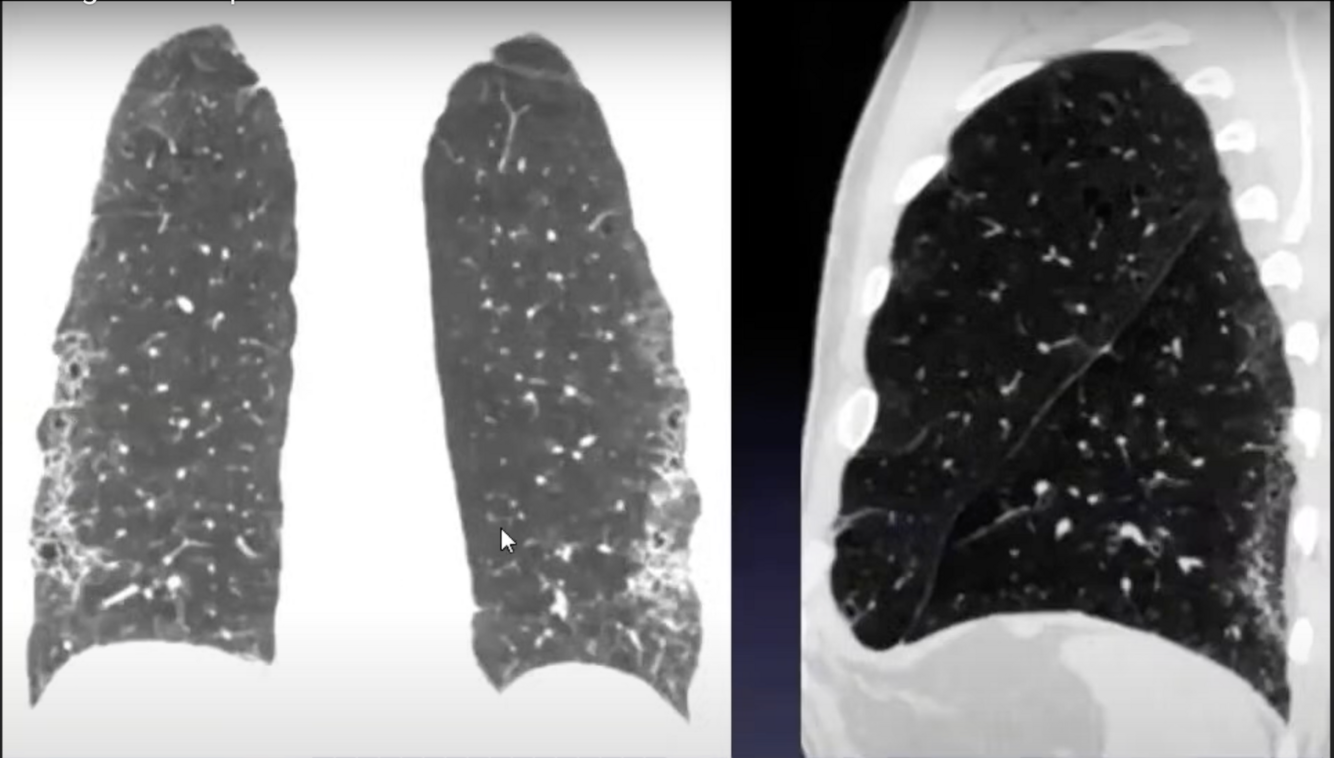

5

Perfectly

6

Q